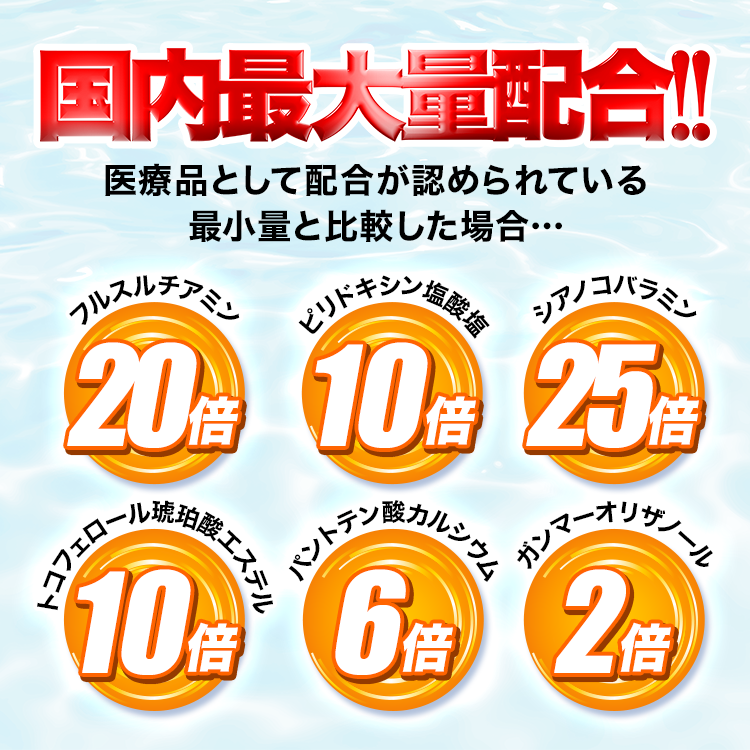

まずはじめにひとことで説明すると、

「ラクーダEXα」とは…

・症状を緩和する成分

・根本原因を改善する成分

が厚労省基準の最大量配合された薬です。

※効果には個人差があります

そのため

しびれや痛みを緩和するだけでなく、

飲み続けることで、

坐骨神経痛の根本原因を改善できるんです!

※効果には個人差があります

気になる人のために

その6つの成分について詳しく説明します。

しかも、6成分すべてが

厚労省基準の最大量配合されているので

間違いなし!